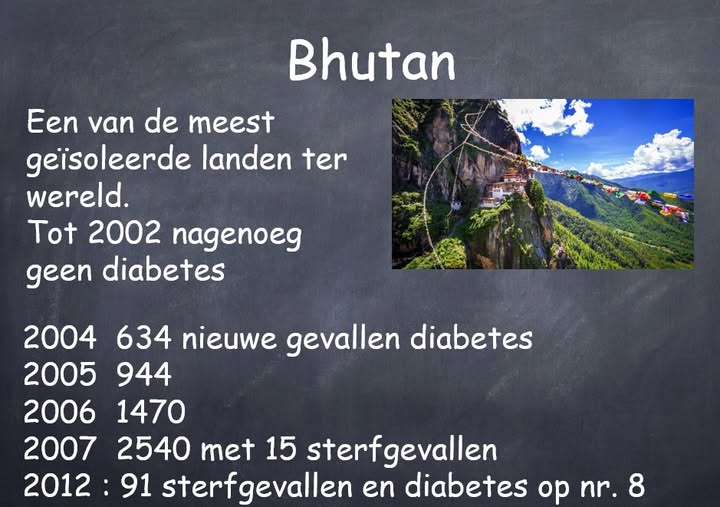

Wat hebben Bhutan en diabetes met elkaar gemeen?

In 8 jaar tijd steeg het aantal diabetici van nagenoeg niets tot volksziekte nummer 1 WAT HEBBEN BHUTAN EN DIABETES MET ELKAAR GEMEEN? Bhutan;